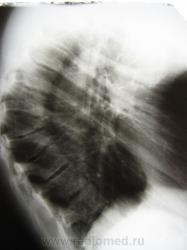

Этому пациенту 16 лет. Кифоз выявлен на проф. осмотре, заподозрена остеохондропатия, направлен на исследование. До этого выставлялась кифотическая осанка в течении 2 лет, какого-то лечения не проводилась. Травму отрицает. Жалобы на боли в спине при небольшой физической нагрузке, длительном сидении. После обследования и учитывая такую степень деформации направлен на МРТ, заключение: остеохондропатия позвоночника. Но после оформления акта на призывника и проведенного обследования куда-то пропал.

А не смущает, что не видно множественных грыж Шморля - сути этого заболевания. Плошадки позвонков выглядят достаточно ровно. Конечно, человек взрослый и здесь если есть, то последствия, площадки должны сгладиться, но не настолько. Они должны быть волнистыми.

Грыжи Шморля есть у клиновидных позвонков, причем, выраженные. А главное, какой кифоз! Никогда такого кифоза не видела при чисто травматических переломах.

Посему, видится мне все таки ВРОЖДЕННЫЙ передний клиновидный позвонок с развитием вторичного остеохондроза в двух сегментах.

Почему - а потому, что клиновидность почти четвертой степени...такая то и при компрессионных переломах то не встречается,(быстрее позвонок разлетится на осколки), а уж при болезни Шойермана-Мау и подавно...чтобы ее получить, эту четвертую степень, надо перелому или быть патологическим...либо с таким позвонком родится.